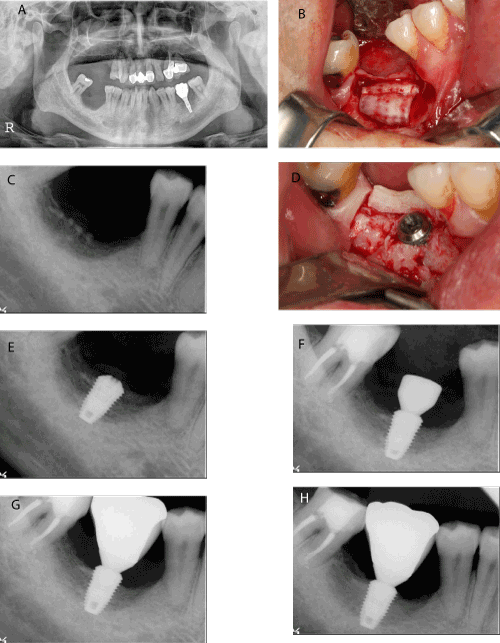

| Figure 2: A case of ridge augmentation using autogenous tooth bone block and chips followed by implant placement in a 39-year-old male patient. A. Pretreatment panoramic radiograph. Notice that the absolute short distance between the residual ridge crest and inferior alveolar nerve canal B. Autogenous tooth bone chips and block (sheet-formed) had been grafted in the site C. Postoperative periapical radiograph D. 6 months later, autogenous tooth bone block was still remained on the graft site and no severe graft material resorption was detected. Then the implant fixture was installed E. Periapical radiograph after implant placement F. The 2nd surgery was done after 3 months. Notice that the peri-implant bone density is getting denser G. Periapical radiograph after prosthetic delivery H. Periapical radiograph 15 months after prosthetic loading. |